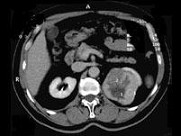

- 多项选择题男性,65岁。左侧腰背部胀痛伴无痛性全程血尿3个月余, CT平扫及增强检查如图所示,下列说法正确的是

A、平扫时见左肾上极有一软组织肿块影,其边界较清楚

B、增强扫描肾皮质期可见肿块明显强化,其内亦有无强化区

C、增强扫描肾实质期可见肿块强化迅速下降,但密度比平扫时仍要高

D、考虑为左侧肾癌

E、考虑为左侧肾错构瘤